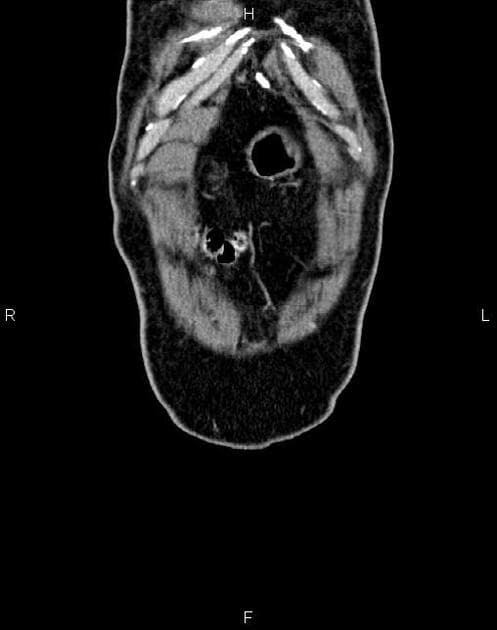

- Dày thành không đối xứng do xâm lấn bởi khối u ở đoạn hai và đoạn ba tá tràng, với sự xâm lấn vào đầu tụy kề bên và gây hẹp lòng tá tràng (duodenal luminal narrowing). Khối u chèn ép tĩnh mạch chủ dưới (IVC) và đẩy lệch các mạch máu mạc treo (mesenteric vessels), nhưng không có xâm lấn hay bao quanh mạch. Ống tụy (pancreatic duct) không giãn.

Chẩn đoán mô bệnh học và miễn dịch hóa học (IHC) xác nhận ung thư biểu mô tuyến tá tràng (duodenal adenocarcinoma) với xâm lấn đầu tụy.

- "Phân biệt ung thư biểu mô tuyến tá tràng với ung thư đầu tụy rất khó; việc xác định chính xác vị trí trung tâm khối u và ống tụy còn nguyên vẹn là dấu hiệu hình ảnh quan trọng."